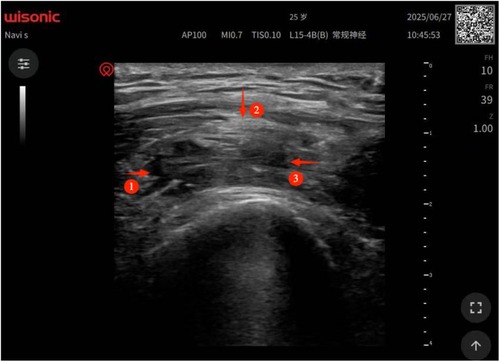

Patients with end-stage hemophilia often require total knee arthroplasty (TKA); however, the incidence of postoperative joint adhesions in these patients is significantly higher than that in the general population. Furthermore, due to their impaired coagulation function, the bleeding risk associated with traditional open adhesiolysis is also higher in this patient cohort than in the general population, and conservative rehabilitation therapy yields suboptimal outcomes. Thus, there is an urgent clinical need for a safe and effective intervention regimen. This study reports a 25-year-old male patient with severe hemophilia A (factor Ⅷdeficiency), whose baseline factor Ⅷactivity was 0.8%. Severe knee joint adhesions occurred 3 months after TKA, manifested as difficulty in walking, sitting, and standing. A combined treatment regimen of "perioperative precise coagulation factor replacement + ultrasound-guided acupotomy release under anesthesia + graded manual release" was adopted for the intervention of post-TKA adhesions in patients with severe hemophilia A. The results showed that this combined regimen may represent a feasible minimally invasive option for the clinical management of post-TKA adhesions in severe hemophilia A patients.